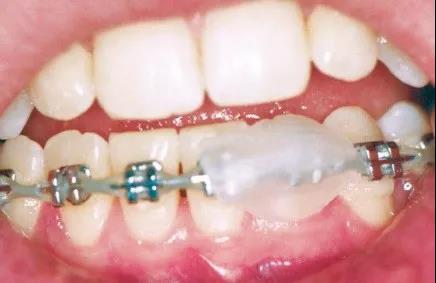

微信图片_20200210130935

微信图片_20200210130937

(3)矫治器脱落:若前面托槽脱落无法取下,可以暂不处理。若为末端颊管脱落,可取下脱落颊管防止误吞,末端弓丝用粘膜保护蜡或口香糖包裹。

微信图片_20200210130940

(4)种植钉松动脱落:松动种植钉暂停橡皮筋牵引,如果种植钉松动度过大或种植钉部位持续疼痛,患者可尝试逆时针轻轻旋转取出种植钉,种植钉取出,可辅助使用维持口腔卫生。

(5)结扎丝或结扎橡皮圈脱落:可以暂时不行处理。